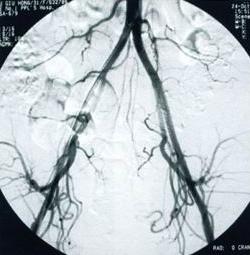

輸卵管導絲擴張疏通術治療步驟

輸卵管鏡、宮腔鏡技術引導檢查

將手術導管通過宮頸放至子宮的開口部位,管中不足毫米的超軟頭納米導絲,在宮腹腔鏡(或X射線)和輸卵管鏡的引導下,通過輸卵管探查、造影、通液等方式,詳細檢查輸卵管病變部位。

納米導絲推進疏通

利用納米導絲的推進、擴張、分離作用和造影劑所產生的衝擊力,快速、安全、有效的使輸卵管疏通至其傘端部位,解決輸卵管的粘連、堵塞問題。